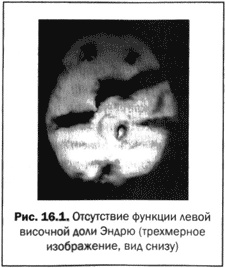

Я повел Эндрю в томографический центр и держал его руку, пока проводили исследование. Когда изображение его мозга появилось на экране, я подумал, что при выполнении процедуры была допущена ошибка. У Эндрю не было левой височной доли (см. рис. 16.1). После быстрой проверки томограммы я понял, что ее качество не вызывало сомнений. У Эндрю действительно отсутствовала функция левой височной доли. Я испугался за него, глядя на монитор, а с другой стороны, испытывал облегчение от того, что мы нашли причину его агрессивного поведения. Мои исследования и исследования других специалистов предполагали, что левая височная доля связана с агрессивностью. На следующий день Эндрю сделали магнитно-резонансную томографию, которая показала кисту (заполненную жидкостью полость) размером с шар для гольфа, она занимала то пространство, где должна была находиться его левая височная доля. Я знал, что кисту надо удалять. Однако найти кого-то, кто бы всерьез отнесся к этому, оказалось делом нелегким.

Иллюстрация к книге — Великолепный мозг в любом возрасте [img22.jpg]